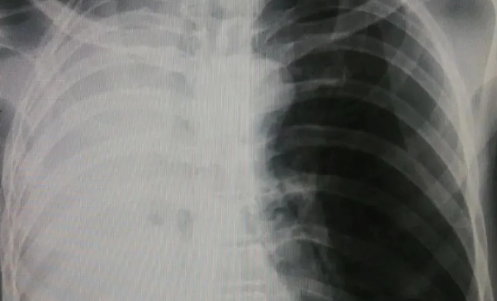

白肺是目前很多人比较担心的问题,因为肺部感染比较严重的话,可能会出现白肺的情况,而不少人不知道白肺到底是什么。那么,白肺症状表现有哪些?白肺治疗要多久能恢复?一起来看看趣丁网带来的详细介绍吧!

白肺症状表现有哪些

1、典型症状:本病最典型的症状是呼吸困难,如果是轻度白肺病,呼吸困难通常发生在剧烈活动时,因此常被忽视,或误诊为其他肺部疾病。随着病情发展,患者在静息状态下也可能出现呼吸困难。

2、其他症状:呼吸困难的患者还会伴有干咳、乏力等症状,有的患者还会出现指间杵状,有的患者还会出现全身不适、体重减轻和发热等症状。

3、并发症状:白肺疾病如果合并肺气肿,患者稍有活动就会出现气短、胸闷和气短症状。严重的情况下,在夜间睡眠时,血液的氧饱和度会显著降低,导致肺动脉增加,从而导致打鼾和呼吸暂停症状。